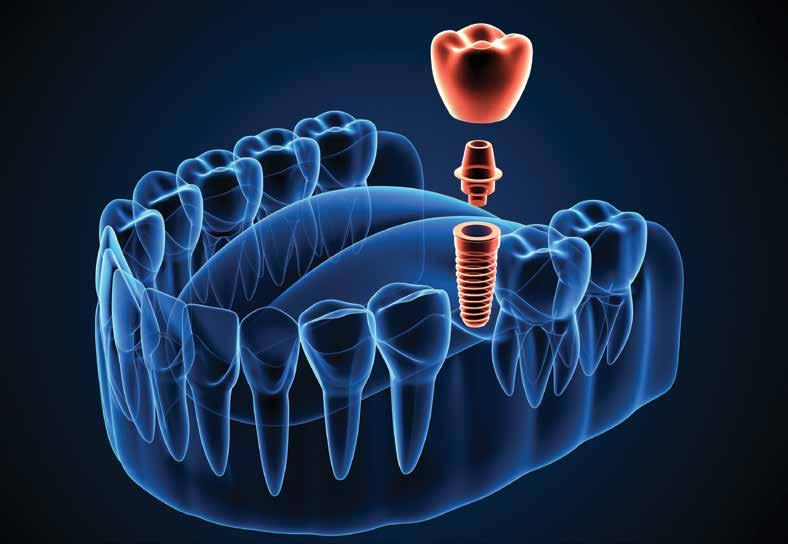

Did you know that the history of dental implants can be traced back to ancient Egypt where they carved seashells and stones to replace missing teeth? As early as 2000 B.C. early versions of dental implants were used in ancient China and the first recorded case of a replacement tooth made of metal came from the body of an Egyptian King around 1000 B.C. That was a long time ago. One of the most important developments that lead to our current dental implants occurred in 1957 when a Swedish orthopedic surgeon named Dr. Per-Ingvar Brånemark began studying bone healing and regeneration and discovered that bone could actually grow in proximity with titanium and could effectively adhere to the titanium and not be rejected. Brånemark called this “osteointegration.”

Now implants are commonplace and they come in many shapes, sizes and different coatings to enable the best integration into bone. In the general population, the use of dental implants has become a great treatment option for replacing missing teeth. It doesn’t matter the age, people want to replace missing teeth and they want to look younger, better and enjoy eating all foods again. Of course, dental implants are not inexpensive and patients can be concerned about finances and length of treatment time. Older adults have complex medical, social and economic issues that must be taken into consideration, and dentists need to give careful attention to help each patient consider the best tooth replacement therapy.

For the majority of the population, the clinical success of dental implant therapy has improved so much that many clinicians consider it to be a standard of care. Tooth replacement therapy can vary from single-tooth replacement with conventional or implant-supported restorations to full-arch replacement. Each option, including no tooth replacement, has advantages and costs that must be weighed in consideration of patients’ desires, understanding, resources and perspectives.

New advances in digital dentistry have enabled more advanced diagnostic information. The dentist can now use a surgical guide or denture to indicate the desired implant position, angulation and need for hard and/or soft tissue augmentation before or during implant placement. Guided implant surgery with the use of cone-beam computed tomography scans and intraoral scanners have made it possible to get the best position and restoration for the patient.